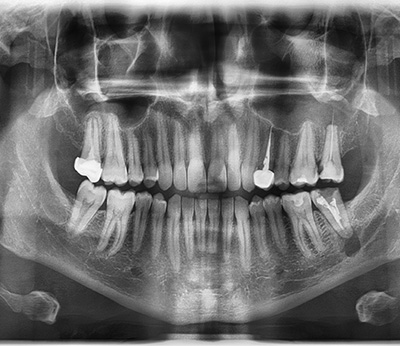

Radiografia digitala panoramica ofera o imagine de ansamblu a ambelor arcade si a intregului set de dinti pe un singur film, în cadrul unei singure expuneri cu o doză de radiaţii redusă într-un timp de examinare foarte scurt. Aceasta radiografie este indicata inaintea oricarui tratament stomatologic, astfel incat medicul sa aiba o imagine completa a cazului pe care il trateaza, sa evalueze eventuale leziuni inflamatorii sau dinti neerupti, structura osoasa de sustinere, articulatiile temporo-mandibulare, sa vizualizeze molarii de minte, rapoartele dintilor cu repere anatomice invecinate (nerv alveolar, sinus maxilar) sau posibile fracturi osoase maxilare sau mandibulare.